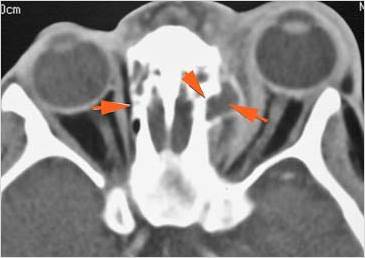

Orbits

The extraconal orbital fat is abnormal.

There is a subperiosteal abscess or edema along the medial wall, roof or floor of the orbit.

The extraocular muscles are swollen or otherwise abnormal.

There is bone erosion along the walls of the orbit.

The superior and/or inferior ophthalmic veins are dilated or thrombosed.